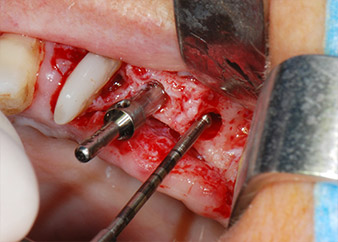

Avant la pose de l'implant, les tissus infectés ont été retirés de l'os alvéolaire sur le site de l'implant et autour des dents piliers à l'aide d'un insert initialement conçu pour le façonnage de l'os et la récupération des copeaux d'os (Piezomed, insert B5) (Figures 6 et 7).

Les lits implantaires ont été préparés sur les sites 25 et 26 à l'aide d'instruments rotatifs, utilisés dans un contre-angle avec un rapport de transmission 20:1 avec un nouveau moteur d'implantologie puissant (Implantmed, W&H) (Fig. 8).